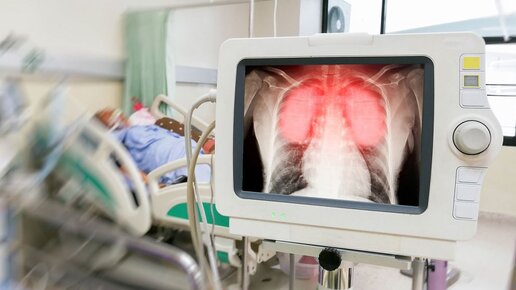

Воспаление легких – самое серьезное осложнение коронавируса. На рентгеновских снимках виден так называемый эффект матового стекла...

Рентген показал, что при коронавирусе происходит с легкими

Коронавирус (COVID-19) вызвал огромный переполох и панику среди населения во всем мире, так как способен привести к тяжелой форме пневмонии, при которой выживают далеко не все пациенты. При пневмонии, вызванной коронавирусом, на рентгене будут четко видны изменения в легких, которые демонстрируют, как он быстро разрушает легочную ткань. По диагнозам врачей такая патология очень схожа с атипичной пневмонией или ближневосточным респираторным синдромом. На рентгеновских снимках пациентов с коронавирусом,...